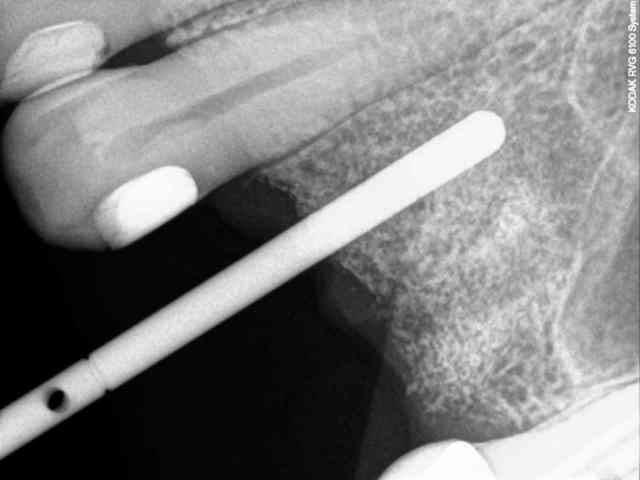

voici le dernier né de la gamme Axiom d'Anthogyr.

il est commercialisé depuis le premier janvier de cette année sauf pour ceux qui ont effectué les essaies cliniques (j'en faisais pas partie--snif!), ceux là pouvaient le commander avant.

les plus:

il a un corps conique et des spires beaucoup plus agressives pour augmenter la stabilité primaire.

son diamètre au niveau du col est légèrement réduit ce qui limite la compression crestal.

on conserve exactement la même connectique que son grand frère l'Axiom REG donc aucun changement pour la prothèse et bien entendu on conserve aussi le platform switching.

le moins:

à éviter sur les os de type D1

le cas que je vous présente date d'hier, il n'a rien d'extraordinaire, alors soyez indulgents, c'était juste pour le plaisir de partager ça avec vous.

7-8-9-10-11- les radios